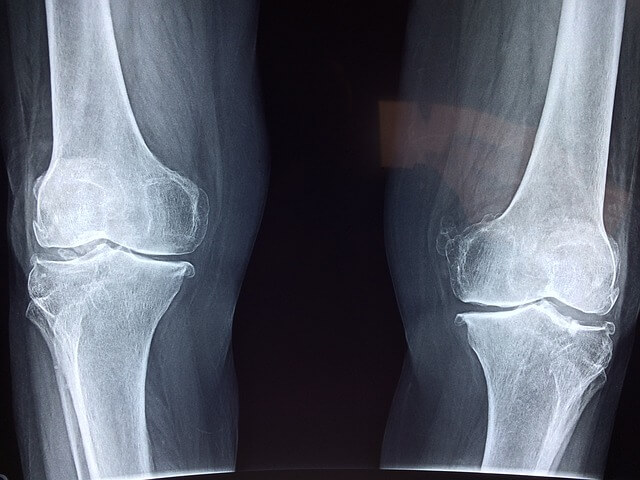

- 퇴행성 관절염: 나이가 들면서 연골이 닳아 무릎에 물이 차는 경우가 많습니다.

무릎에 물이 차면 나타나는 증상

무릎에 물이 차는 경우 다음과 같은 증상들이 동반될 수 있습니다.

- 무릎 부종: 무릎이 붓고 부피가 증가합니다.

- 통증: 움직이거나 눌렀을 때 통증이 발생할 수 있습니다.

- 운동 제한: 관절의 움직임이 제한되거나 뻣뻣함을 느낄 수 있습니다.

- 열감: 무릎 부위가 뜨겁게 느껴질 수 있습니다.

- 눌렀을 때 물소리: 무릎을 누를 때 물이 움직이는 소리가 날 수 있습니다.